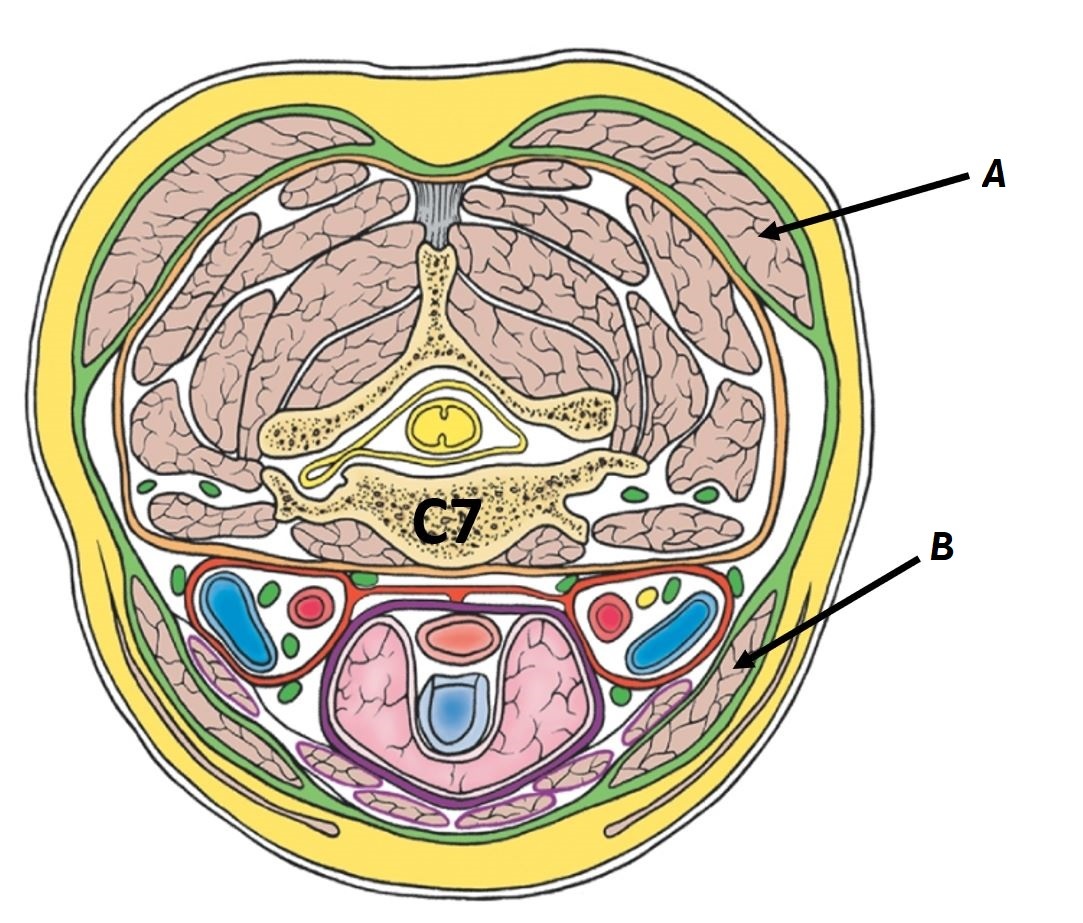

Name structures A to D

A - Strap muscles

B - Thyroid gland

C - Trachea

D - Oesophagus

Name structures A, B and C

A - Right carotid sheath

B - Pretracheal fascia

C - Left lobe of thyroid gland